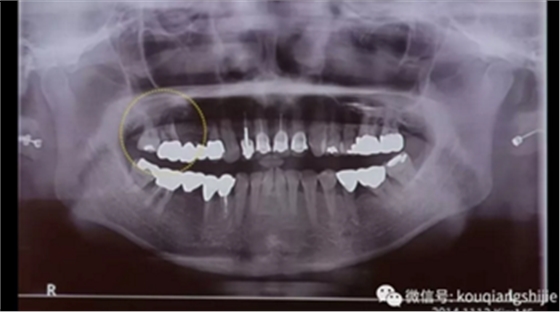

我们可以看到#17,18的牙周炎非常严重

从CT上我们可以看到骨破坏非常严重

拔牙后也将拔牙窝内的黏膜提拉上来

十周之后我们可以看到黏膜组织没有出现凹陷

翻瓣之后可以看到形成的充足的骨量